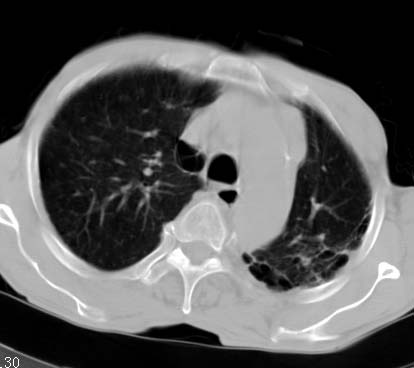

男性病人 81岁 胸痛 咳嗽2月 2周前提示右下肺感染.

今片ct示双肺多发结节影 可以这样诊断吗?1\双肺感染性病变 结核待排.

2\双肺纤维硬结灶,左肺肺气肿.

3\肺间质纤维化,胸膜肥厚粘连.

纵隔左移双肺上叶纤维硬结,肺气肿,双侧斑痕肺大泡,双侧胸膜增厚并胸膜下陈旧性病灶,右肺下叶胸膜下小结节影,密度较淡,建议复查.

病人桶状胸,胸廓肌肉消瘦;两上肺均可见纤维条索灶,下肺外围胸膜下可见间质纤维化改变,右下肺沿肺纹理分部结节样病灶,边缘光滑,考虑1、慢支并局灶性间质纤维化、右下肺合并感染,2、两上肺为陈旧性肺结核灶并瘢痕旁型肺气肿3、右下肺转移瘤待排。

两肺上叶见多发索条状高密度影,右肺下叶见片状、结节状高密度影,两肺体积增大,胸膜下区见囊状低密度影、内有分隔结构。左肺下叶见网格影。两侧胸膜见增厚影。诊断:两肺继发性肺结核。慢性支气管炎合并感染。肺气肿。肺间质纤维化。胸膜增厚。